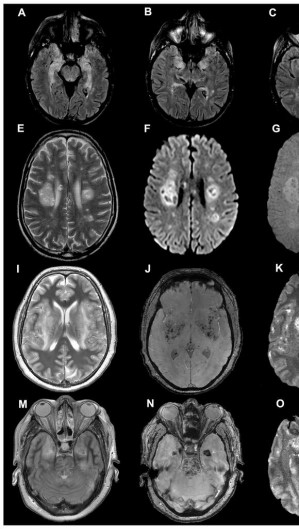

Além de ser uma doença respiratória, a Covid-19 também afeta o cérebro humano, provocando manifestações como delírios e perda de olfato e/ou paladar. Não é de se estranhar: evidências já demonstravam que os coronavírus Sars-Cov (2002) e Mers (2012) também infectavam o cérebro, induzindo a encefalites, encefalopatia e Acidentes Vasculares Cerebrais (AVCs). O apresentador do SportTV, Rodrigo Rodrigues morreu, em julho, vítima de complicações neurológicas após a Covid-19.

No entanto, o Sars-Cov-2, vírus causador da Covid-19, parece ter mais efetividade ao alcançar o sistema nervoso. Isso faz com que ele provoque manifestações mais intensas em comparação aos outros coronavírus. Assim, estima-se que cerca de 40% das pessoas contaminadas com o novo coronavírus apresentam sintomas neurológicos.

Uma certeza é de que a Covid-19 ataca os neurônios, como indicado por pesquisa da Universidade de Yale, ainda em preprint (que ainda precisa de revisão de outros pesquisadores) e publicada dia 8 de setembro de 2020.

A pesquisa demonstrou que o vírus atinge principalmente o córtex, a parte mais superficial do cérebro. De acordo com as observações, o Sars-Cov-2 não destrói as células infectadas, mas parece suprimir a comunicação com outras células e “sugar” o oxigênio delas, provocando a morte da região ao redor do organismo.

“É muito preocupante que o Sars-Cov-2 infecte neurônios do córtex cerebral. Ainda mais preocupante é que não se encontrou no tecido cerebral grande infiltrado imune, sugerindo que a resposta imune pode ser inadequada no cérebro”, analisa o neurocientista. Segundo ele, ainda há muito a se estudar sobre a resposta imunológica do corpo humano à Covid-19 no órgão.